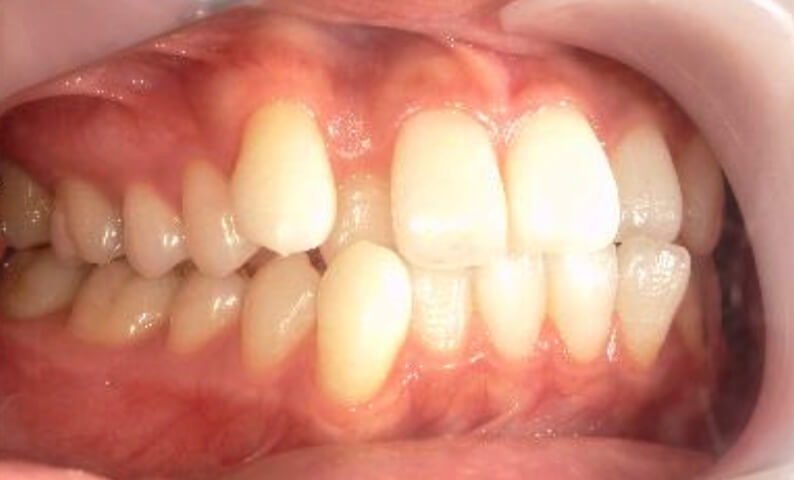

症例_018 上顎だけの部分矯正

治療期間:7ヶ月金額:30万円+税女性前歯のガタガタ上の前歯だけ

| Before | After |

|---|---|

|